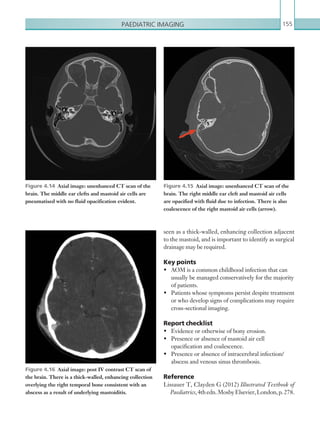

• 80.

Chapter 258 Radiological findings Computedtomography The presence of extraluminal oral contrast in the posterior mediastinum (which can also track into the left-sided pleural cavity) is indicative of oesophageal perforation (Figures 2.48, 2.49). An additional helpful signispneumomediastinum;utilisationoflungwindow settings aids visualisation of this (Figure 2.50). It should be noted that this is a non-specific sign and if seen in isolation, additional causes should be considered (Table 2.15). Concentric or eccentric oesophageal muralthickeningcanalsobeseenincasesofoesophageal perforation, although it is also non-specific and can be seen with oesophagitis or malignancy; the presence of associated para-oesophageal lymphadenopathy is more suggestive of the latter. Para-oesophageal enhancing fluid collections may also be seen. Note: Small oesophageal leaks may be missed on CT, especially in the absence of oral contrast; this should be emphasised in the report. Fluoroscopy Contrast swallow fluoroscopy should be performed with the patient in a semi-supine (20°) position, right Figure 2.48  Axial image: oral and IV contrast enhanced CT scan of the thorax in the arterial phase. Oral contrast is seen collecting in the right pleural space with locules of gas. Left pleural effusion is also noted. Figure 2.49  Axial image: oral contrast CT scan of the thorax. Contrast can be seen within the stomach. Contrast has collected around the oesophagus within the posterior mediastinum (arrow). A left-sided pleural effusion is also present, containing locules of gas. Figure 2.50  Axial image: IV contrast enhanced CT scan of the thorax in the arterial phase. Viewed on lung window settings, gas can be seen surrounding the ­superior mediastinal structures. andleftanterioroblique,rightandleftlateralandprone positions, although this depends on patient tolerance. Ideally, the patient should swallow the oral contrast mediumfromacupondemand.Bolusesoforalcontrast K22247_C002.indd 58 16/05/15 3:07 AM

• 81.

Gastrointestinal and genitourinaryimaging 59 • Blunt chest trauma. • Secondary to chest, neck or retroperitoneal surgery. • Oesophageal perforation. • Tracheobronchial perforation. • Vigorous exercise. • Asthma. • Barotrauma. • Subcutaneous emphysema, pulmonary interstitial emphysema. • Stab wound. • Infection. • Idiopathic. Table 2.15  Causes of pneumostinum. Figure 2.51  PA chest radiograph. Streaky linear ­lucencies are seen within the superior mediastinum and outlining the left heart border. Subcutaneous ­emphysema is also seen in the supraclavicular fossa bilaterally. Reference Tonolini M, Bianco R (2013) Spontaneous esophageal perforation (Boerhaave syndrome): diagnosis with CT-esophagography. J Emerg Trauma Shock 6:58–60. should be followed down the entire oesophagus. Rupture is confirmed in the presence of extravasation of oral contrast or an irregular collection of contrast external to the oesophageal lumen. Additional findings include oesophageal wall irregularity and distortion, which may suggest para-oesophageal collections. Adequate oesophageal luminal distension is vital to identify oesophageal perforation; this requires a good oral contrast load. The study should always be terminated if oral contrast material is aspirated. Plain films Chest plain film findings are all non-specific but can suggest the diagnosis of oesophageal perforation. The most common sign of oesophageal perforation seen on chest plain film imaging is a left-sided pleural effusion and atelectasis/consolidation, reflecting the fact that the most common site of oesophageal perforation is the distal left-sided posterior wall. Pneumomediastinum should always raise suspicion of oesophageal perforation, especially in the presence of associated symptoms. Pneumomediastinum has many appearances on chest plain film imaging, although all rely on the presence of abnormal gas outlining the normal mediastinal structures (Figure 2.51). Note: Pneumomediastinum on plain film imaging has a low sensitivity and specificity for oesophageal rupture and can be seen in many other conditions (Table 2.15). Key points • Oesophageal perforation has a high mortality rate and urgent diagnosis is essential. • Imaging modalities include CT with water soluble oral contrast and fluoroscopy. Small leaks can be missed on both modalities if the oral contrast load is inadequate. Report checklist • Presence or absence of extra-oesophageal oral contrast. • Attempt to localise any potential oesophageal breach. • Document any associated complications (e.g. mediastinal collections and mediastinitis). K22247_C002.indd 59 16/05/15 3:07 AM

• 82.

Chapter 260 and non-compression)is most diagnostic in the hands of experienced sonographers and radiologists. In the on-call setting, the use of ultrasound and experience in scanning for appendicitis may be limited. (See Table 2.16.) Radiological findings Computed tomography The appendix should be identified – the use of multiplanar reformatting is sometimes necessary to achieve this. The normal appendix appears as a tubular or ring-like pericaecal structure that is either totally collapsed or partially filled with fluid, contrast material or air. It has a thickness less than 3 mm. Acute appendicitis causes thickening of the appendix with a two-wall diameter greater than 6–7 mm. Periappendicular inflammatory stranding and free fluid may also be seen (Figure 2.52), as may a calcified appendicolith (seen in 30% of cases, Figure 2.53). Other conditions, such as active Crohn’s disease in the terminal ileum, can cause a similar appearance of a thickened tubular structure in the right iliac fossa. It is important to differentiate the two structures anatomically, since the management of the two conditions differs. Caecal thickening and inflammatory changes may be present, and if oral contrast has been given, it may give rise to an ‘arrowhead’ appearance, as contrast funnels at the caecal apex to the point of the obstructed appendicular orifice. Perforated appendicitis is usually accompanied by pericaecal abscess formation, which presents as an enhancing fluid collection (Figure 2.54). These may ACUTE APPENDICITIS Acute appendicitis is the most common cause of acute abdominal pain and is a surgical emergency. Appendicitis occurs in all age groups; it is rare in infants but becomes increasingly common in childhood, reaching peak incidence in the late teenage years and early twenties. Abdominal pain is the primary symptom of appendicitis and is initially located in the lower epigastrium or periumbilical area. The pain subsequently localises to the right lower quadrant, where it becomes progressively more severe. Anorexia nervosa nearly always accompanies appendicitis. Nausea, vomiting and low-grade fever are common symptoms. Less commonly, diarrhoea or constipation may be seen. The physical examination findings in acute appendicitis are localised abdominal tenderness, rigidity, muscle guarding, pain on percussion and rebound tenderness. Pain in the right lower quadrant with palpation of the left lower quadrant (Rovsing sign) is helpful in supporting a clinical diagnosis. High C-reactive protein (0.8 mg/dl) with leucocytosis and neutrophilia is the most significant laboratory finding. The diagnosis of acute appendicitis is primarily a clinical one; however, many conditions have similar clinical presentations to appendicitis and a definitive diagnosis may be difficult to make. In these cases of clinical uncertainty, the on-call radiologist may be required to aid the diagnosis. Radiological investigations Both CT and ultrasound can be useful in the diagnosis of acute appendicitis and its complications. Radiology, primarily CT, can reduce the number of misdiagnoses and negative laparotomies, with high positive and negative predictive values of between 95 and 98% and 95 and 100%, respectively (Curtin et al., 1995). In addition,itcanbeofuseinthedetectionofappendicular abscesses, postoperative complications and other conditionsmimickingappendicitis.Ultrasoundalsohas a diagnostic role in patients where CT is less favourable (e.g. children, young women and pregnant women). The reported positive and negative predictive values are 91 to 94% and 89 to 97%, respectively (Curtin et al., 1995). The use of ultrasound (compression MODALITY PROTOCOL CT Post IV contrast, portal venous phase: 100 ml IV contrast, 4 ml/sec via 18G cannula. Scan at 70 seconds. Scan from above diaphragm to femoral head level. Ultrasound 6–9MHz linear probe. Table 2.16 Acute appendicitis. Imaging ­protocol. K22247_C002.indd 60 16/05/15 3:07 AM

• 83.

Gastrointestinal and genitourinaryimaging 61 Figure 2.52  Coronal image: oral and IV contrast enhanced CT scan of the abdomen and pelvis in the portal venous phase. A thick-walled appendix can be seen in the right iliac fossa (arrow). There is adjacent inflammatory fat stranding. Figure 2.53  Axial image: oral and IV contrast enhanced CT scan of the abdomen and pelvis in the portal venous phase. A thick-walled appendix can be seen in the right iliac fossa containing a round calcified appendicolith (arrow). Figure 2.54  Axial image: oral and IV contrast enhanced CT scan of the abdomen and pelvis in the portal venous phase. A relatively well-defined mass is seen in the right iliac fossa just anterior to the right psoas muscle (arrow). An abscess has formed around the appendix, with inflammatory changes visible around the mass. K22247_C002.indd 61 16/05/15 3:07 AM

• 84.

Chapter 262 may alsobe increased echogenicity of the mesenteric fat that surrounds the appendix. Adjacent hypoechoic free fluid may also be seen, in addition to focal abscess formation. Key points • Appendicitis is primarily a clinical diagnosis. Radiology should only be used in situations where the clinical diagnosis is uncertain. • Ultrasound can be used in cases where CT is less favourable (i.e. children and pregnant women), but it is is user dependent. • Key CT features include a thickened appendix (6 mm), surrounding inflammatory mesenteric changes and the presence of an appendicolith. Report checklist • Document the diameter of the appendix and the degree of appendicular thickening. • Presence or absence of complications, such as appendicular abscesses and perforation. References Brown M (2008) Imaging acute appendicitis. Semin Ultrasound CT 29:293–307. Curtin K, Fitzgerald S, Nemcek A et al. (1995) CT diagnosis of acute appendicitis: imaging findings. Am J Roentgenol 164:905–909. involve adjacent structures (Figures 2.55a–c). Free intraperitoneal gas is suggestive of appendicular perforation without abscess formation, and is best appreciated on lung or bone window settings. As with any cause of intra-abdominal inflammation, acute appendicitis can cause localised small bowel ileus, suggested by small bowel dilatation without an associated transition point. Sagittal and coronal reformats can help to identify the appendix when it is difficult to find. They can also be used to identify where abscesses are tracking, and the nature of their relationship to the appendix. Ultrasound Appendicitis is diagnosed on ultrasound when the total appendix diameter is greater than 6 mm or individual wall thickness is greater than 3 mm (Brown, 2008). The diagnosis is also suggested by a ­non-compressible appendix during scanning (Figures 2.56a, b). A technique of graded compression should be adopted. This requires the operator to gradually increase pressure on the patient during the scan over the site of tenderness, in order to displace loops of bowel and demonstrate the appendix. In normal patients, it can be difficult to visualise the appendix. An appendicolith appears as a focal hypoechoic structure within the tubular appendix, which usually demonstrates posterior acoustic shadowing. These are often present in patients with acute appendicitis. There K22247_C002.indd 62 16/05/15 3:07 AM